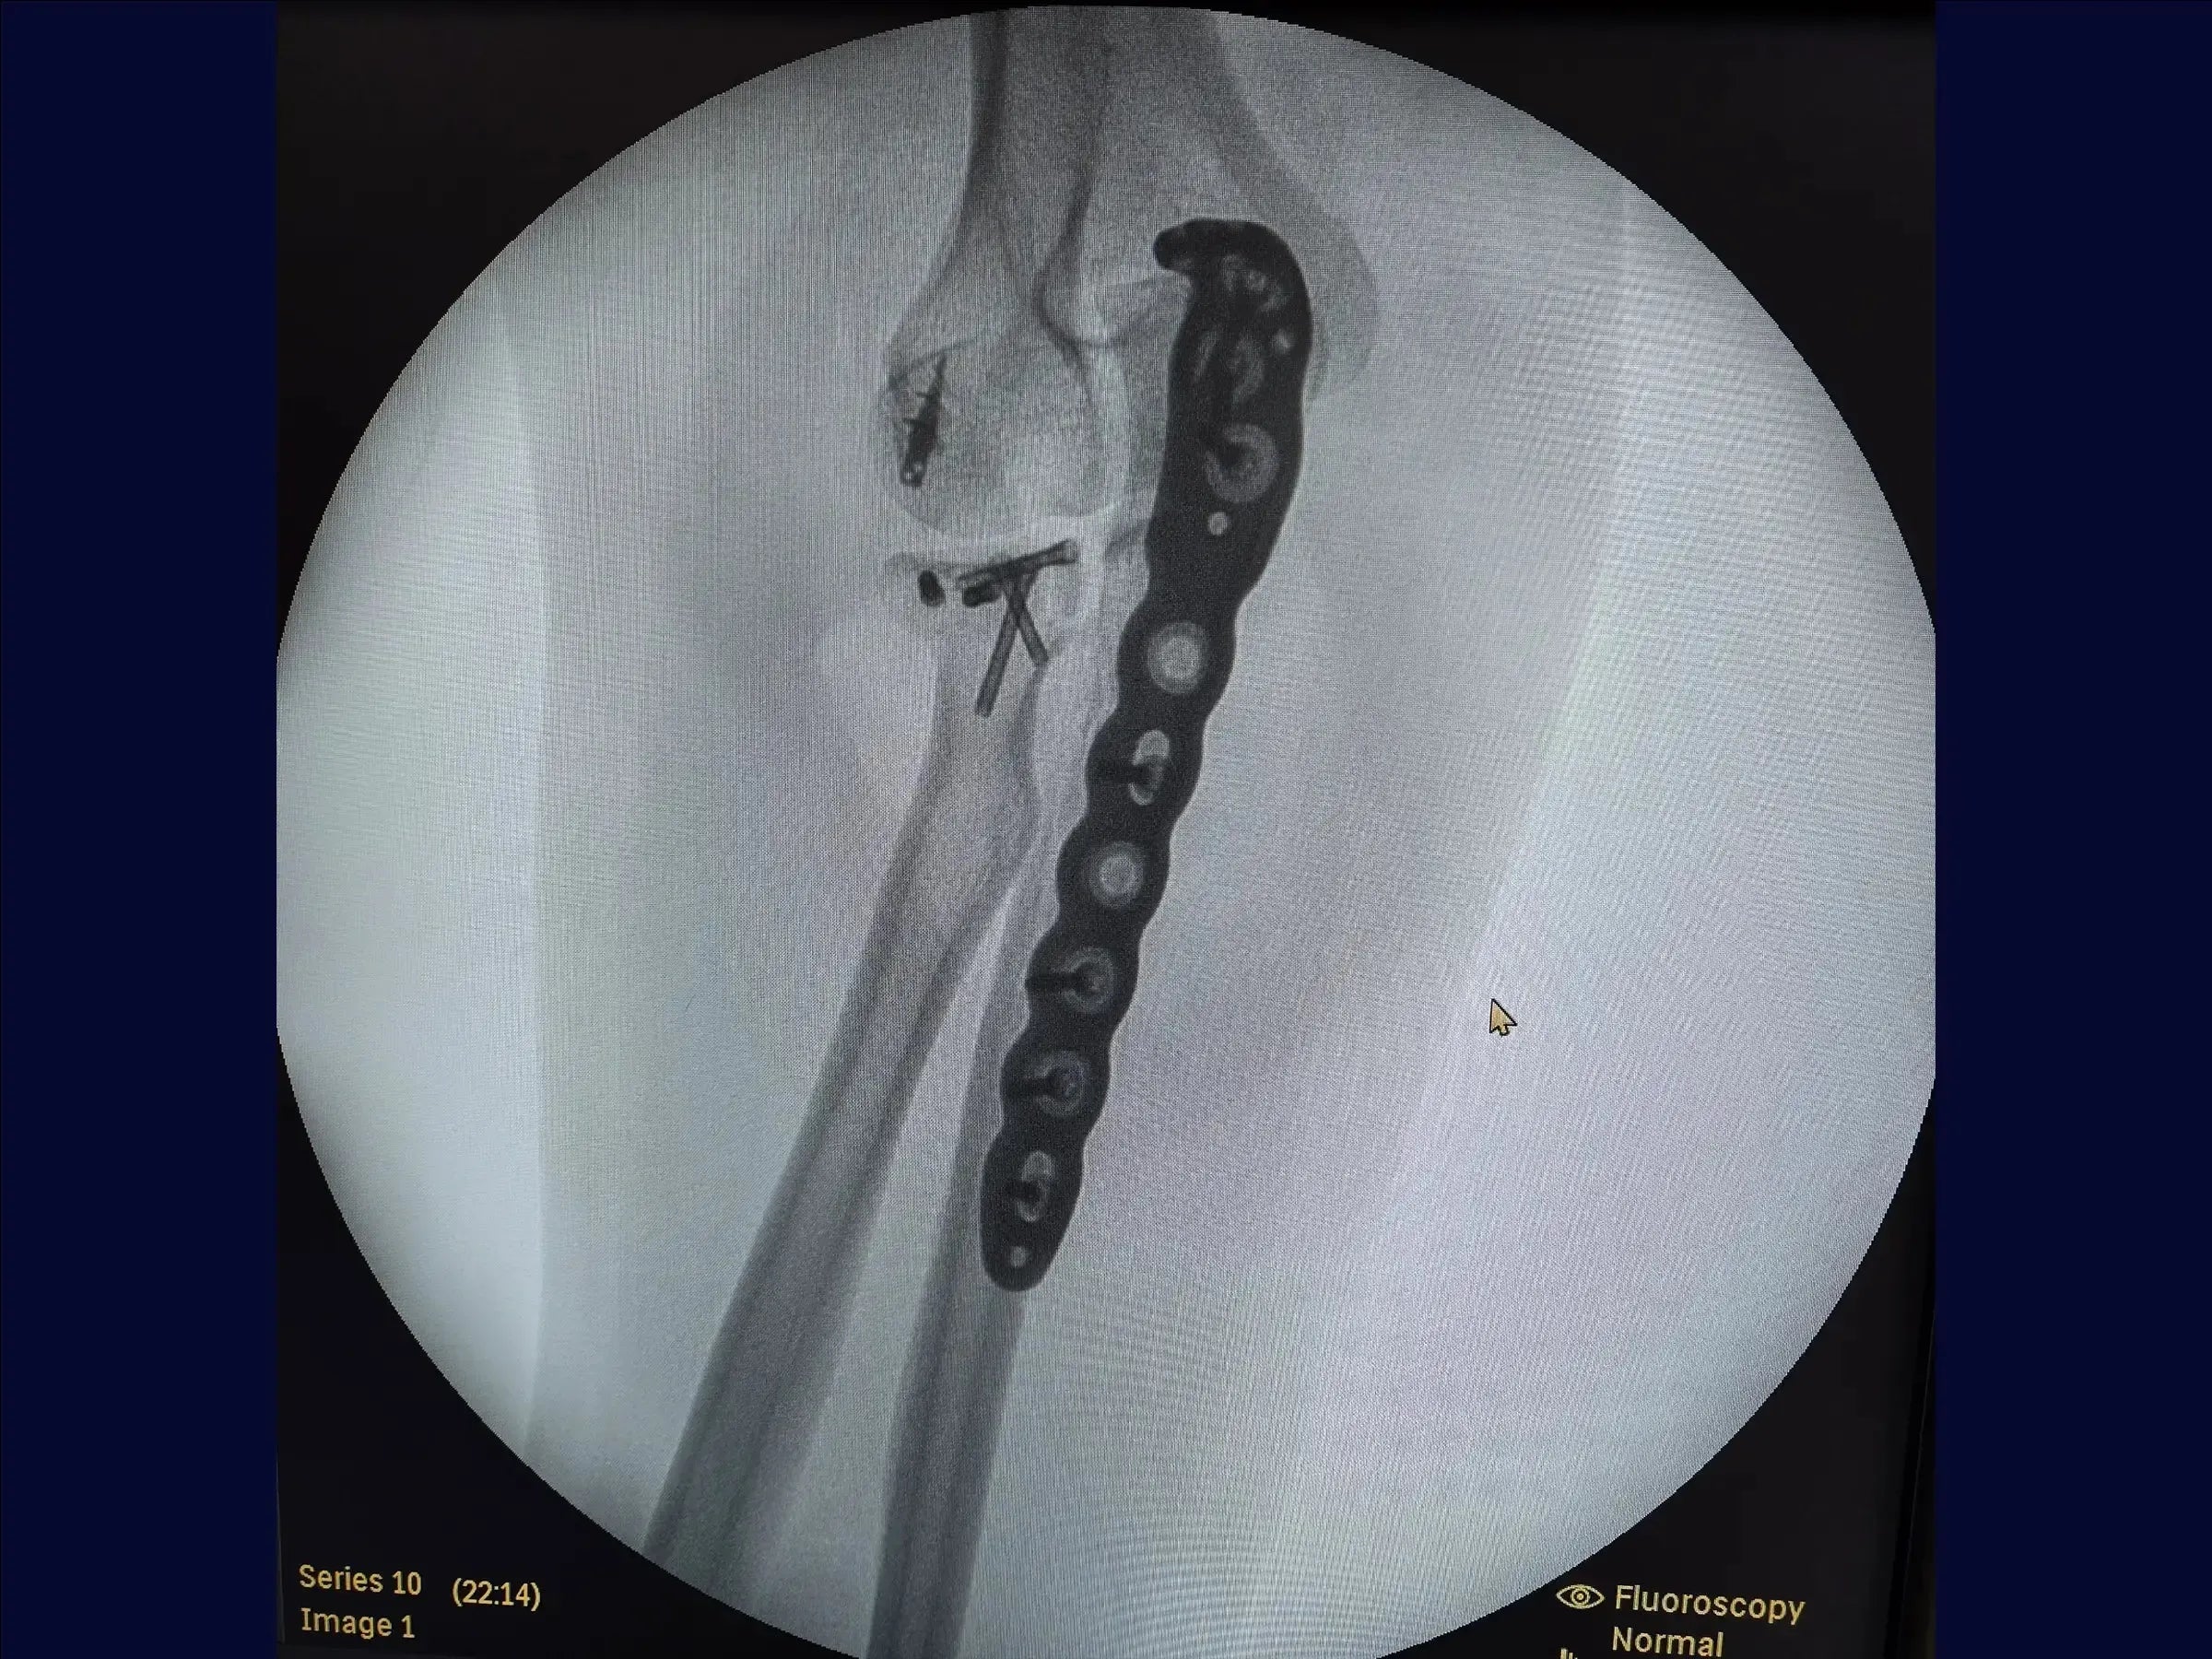

Fractura metafisaria del cúbito proximal con luxación y fractura de la cabeza radial (variante de Monteggia)

Mejore sus habilidades en el tratamiento de una de las lesiones de codo más complejas: la fractura metafisaria del cúbito proximal asociada a la luxación posterior y la fractura de la cabeza radial, conocida como variante de Monteggia . Esta formación abarca la reducción anatómica del cúbito y la cabeza radial, la fijación con placas y tornillos, y la reinserción de estructuras ligamentosas, con el objetivo de restaurar la estabilidad articular y permitir la movilidad temprana del codo, minimizando el traumatismo tisular y optimizando el resultado estético.

- Fijación estable con placas y tornillos.

- Fijación del cúbito : reducción anatómica del componente metafisario y preparación del lecho para la colocación de la placa con mínima lesión muscular.

- Placas y cierre: Fijación progresiva con tornillos dinámicos y bloqueados. Cierre anatómico de la fascia y la aponeurosis, guiado mediante marcas cutáneas.